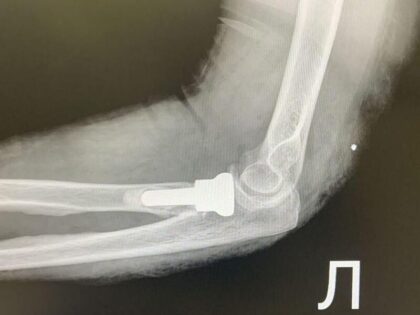

Первой пациентке 66 лет — у неё диагностировали оскольчатый перелом головки лучевой кости. Второй случай сложнее: 55-летняя женщина получила множественные травмы — перелом метаэпифиза левой лучевой кости, перелом локтевой кости в верхней трети и оскольчатый перелом головки лучевой кости.

Но при оскольчатых переломах головки лучевой кости, когда она дробится на множество фрагментов, ситуация иная. Собрать мелкие осколки и надёжно зафиксировать их пластиной практически невозможно. Требуется другой подход.

Решение: эндопротез

Врачи выбрали протезирование головки лучевой кости. Суть операции в следующем:

- удаляют повреждённые костные фрагменты;

- формируют костномозговой канал в проксимальном отделе лучевой кости;

- устанавливают эндопротез из биосовместимого материала.